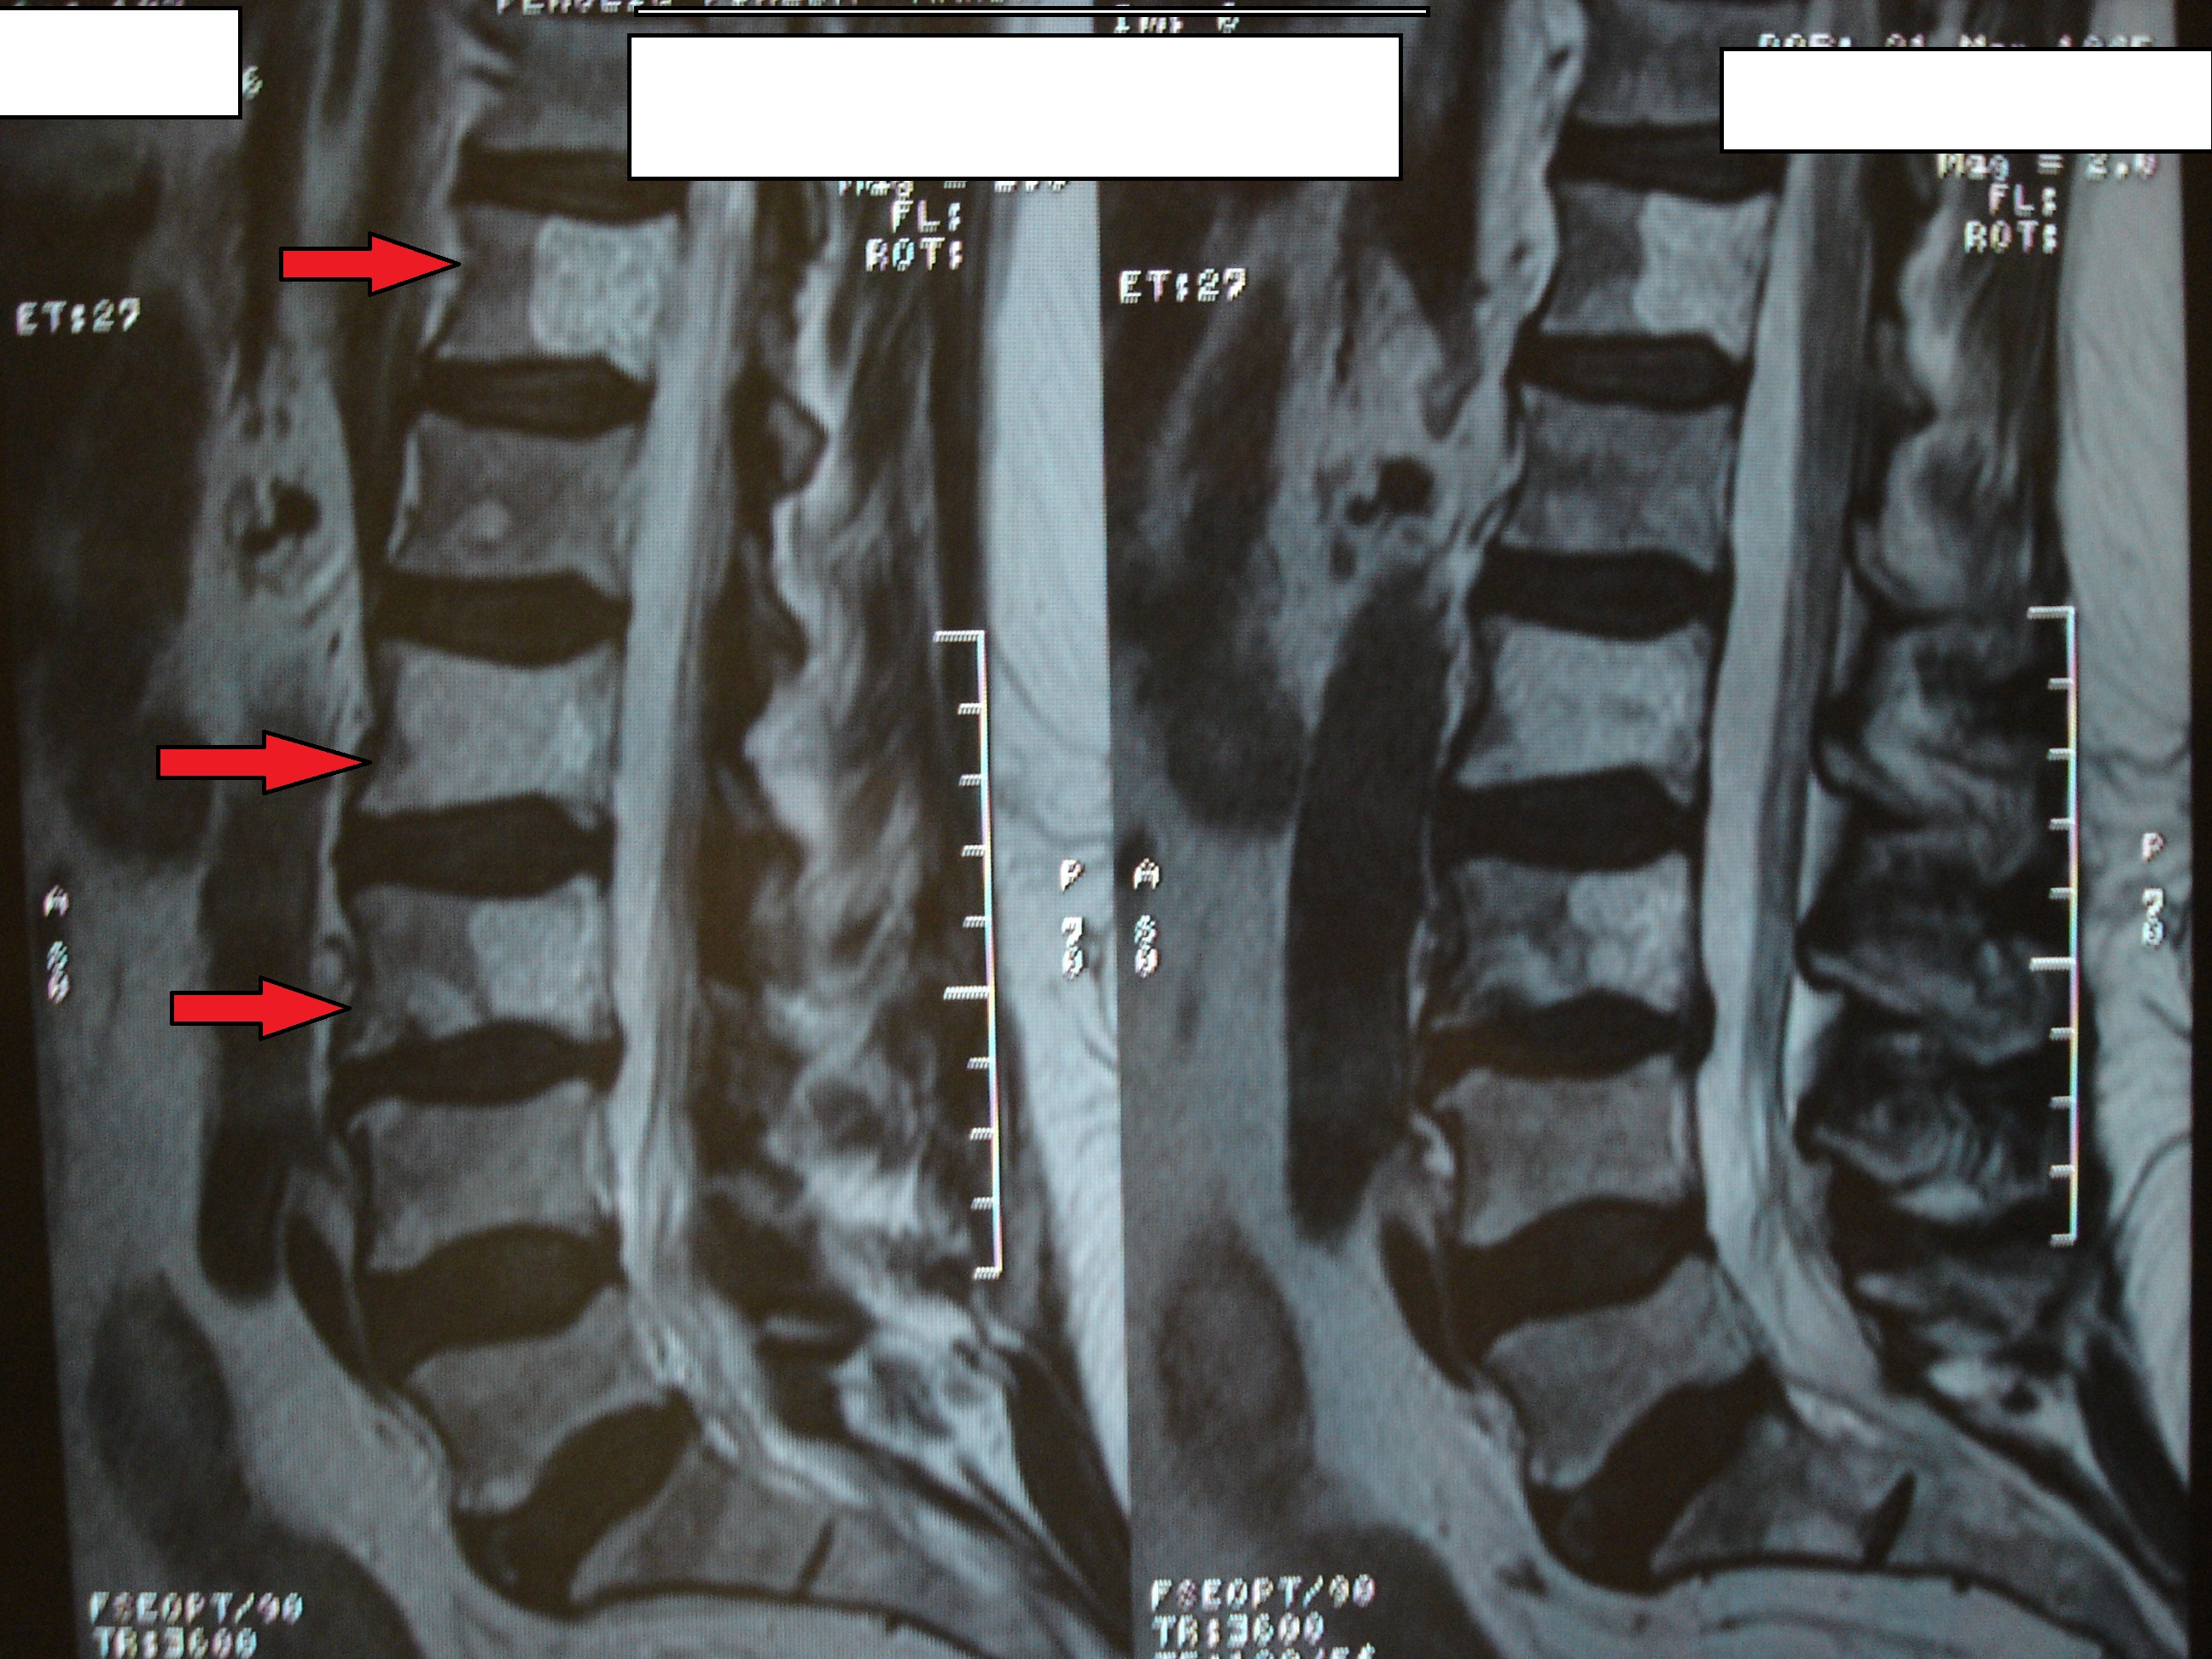

Las imágenes a continuación pertenecen a un caso con una remisión sintomática casi completa y un grado muy alto de satisfacción de la paciente tratada.

En las imágenes de RX y RMN se observan los cambios degenerativos (señalados en rojo las articulaciones interapofisarias artrósicas), también la presencia de múltiples hemangiomas, y las imágenes intraoperatorias de control de los implantes de oro (con flechas).